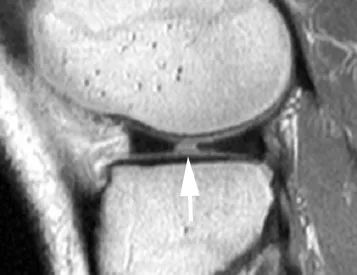

Perpendiculaire au plan tibial et le long de la circonférence du ménisque.Ceux-ci affectent plus fréquemment le ménisque médial.Une blessure complète est considérée comme instable et divise le ménisque en segments médial et latéral.Le niveau de numérisation comprend également le corps du ménisque latéral et la corne postérieure du ménisque, ce qui est facile à mal diagnostiquer comme une déchirure de la poignée du barillet, ce qui est plus susceptible de se produire lorsque l'articulation du genou est tournée vers l'extérieur.Combiné avec des images sagittales, une déchirure en anse de tonneau peut être exclue (Figure 3).

A. IRM coronale, la flèche pointe vers la corne postérieure du ménisque latéral, qui peut facilement être confondue avec une fissure en anse de barillet ;B. Lors de l'exécution d'un balayage IRM selon la position indiquée par la ligne pointillée sur la figure, une pseudo déchirure de la poignée du barillet apparaîtra.